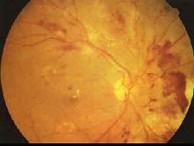

糖尿病眼部病变中导致失明的主要原因是 ( )A、视网膜小静脉扩张B、增殖性视网膜病变C、微血管瘤D、硬性渗出E、白内障

问题 糖尿病眼部病变中导致失明的主要原因是 ( )

选项 A、视网膜小静脉扩张 B、增殖性视网膜病变 C、微血管瘤 D、硬性渗出 E、白内障

答案 B